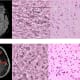

In a recently published study, the UC San Francisco Brain Tumor Center team validated a novel optical imaging technique called stimulated Raman histology (SRH) for rapid, intraoperative detection of glioma infiltration at the tumor margin. This method yields images within minutes for microscopic detection of residual tumor cells—information that can help guide decisions on the extent of resection and improve patient survival rates.

Identification of tumor cells on a microscopic level is normally a time- and labor-intensive process, not feasible for intraoperative rapid detection. SRH is a nondestructive, rapid, label-free technique that provides imaging of unprocessed surgical tissues at microscopic resolutions.

Researchers found agreement when comparing SRH images with IHC and H&E stains

When comparing the SRH images of the 179 margin samples to images of the same samples produced using standard microscopic detection methods, the UCSF researchers found excellent agreement with immunohistochemistry (IHC) and hematoxylin and eosin (H&E) stains. SRH imaging can generate pseudo-H&E images within minutes, allowing for microscopic-level identification of residual tumor cells during surgery. Not previously validated in the intraoperative setting, this innovative technique has the potential to significantly increase the amount of tumor that can be removed and therefore improve survival rates for patients with brain tumors.